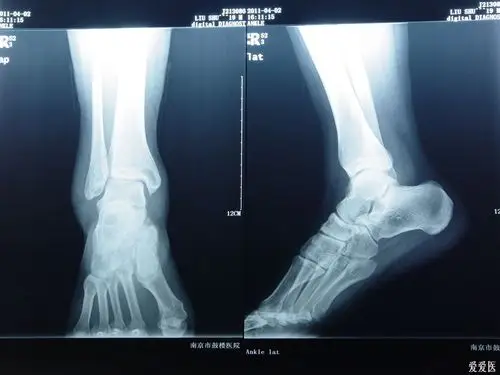

x光片